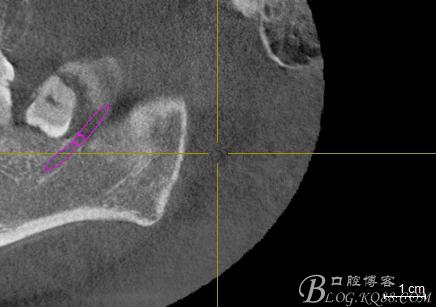

口內(nèi):38未萌出。37遠(yuǎn)中牙周袋10mm,CT:38牙冠倒置。牙齦紅腫,捫診可有少量血性滲出,無(wú)波動(dòng)感。印象診斷:38冠周炎。處理:1.抗炎治療,改善張口度。2.炎癥消退后,拔除38.

一、術(shù)前CBCT影像資料